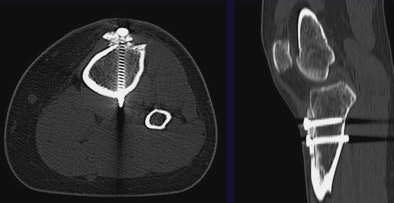

![]() |

| Correct placement of the orthopedic plate and screws are investigated in wrist images. MDCT shows a cystic change and some widening of the scaphoid bone. It appears that at least two of the screws are in the radiocarpal joint, resulting in a recommendation that the orthopedic hardware be replaced. |